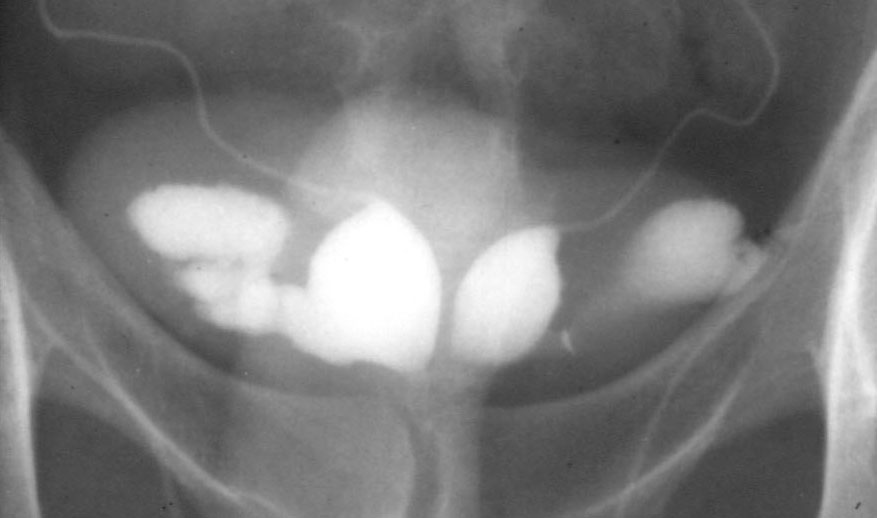

Obstruction could be diagnosed by vasography (pictured right) / ultrasound or, of course, from a past history of vasectomy. It could be treated by vasectomy reversal, epididymo-vasostomy for epidiymal obstruction due to infection or endoscopic deroofing of the obstructed seminal vesicles for ejaculatory duct obstruction; the latter could also be diagnosed by an absence of fructose in the ejaculated semen (fructose is produced exclusively in the seminal vesicles).